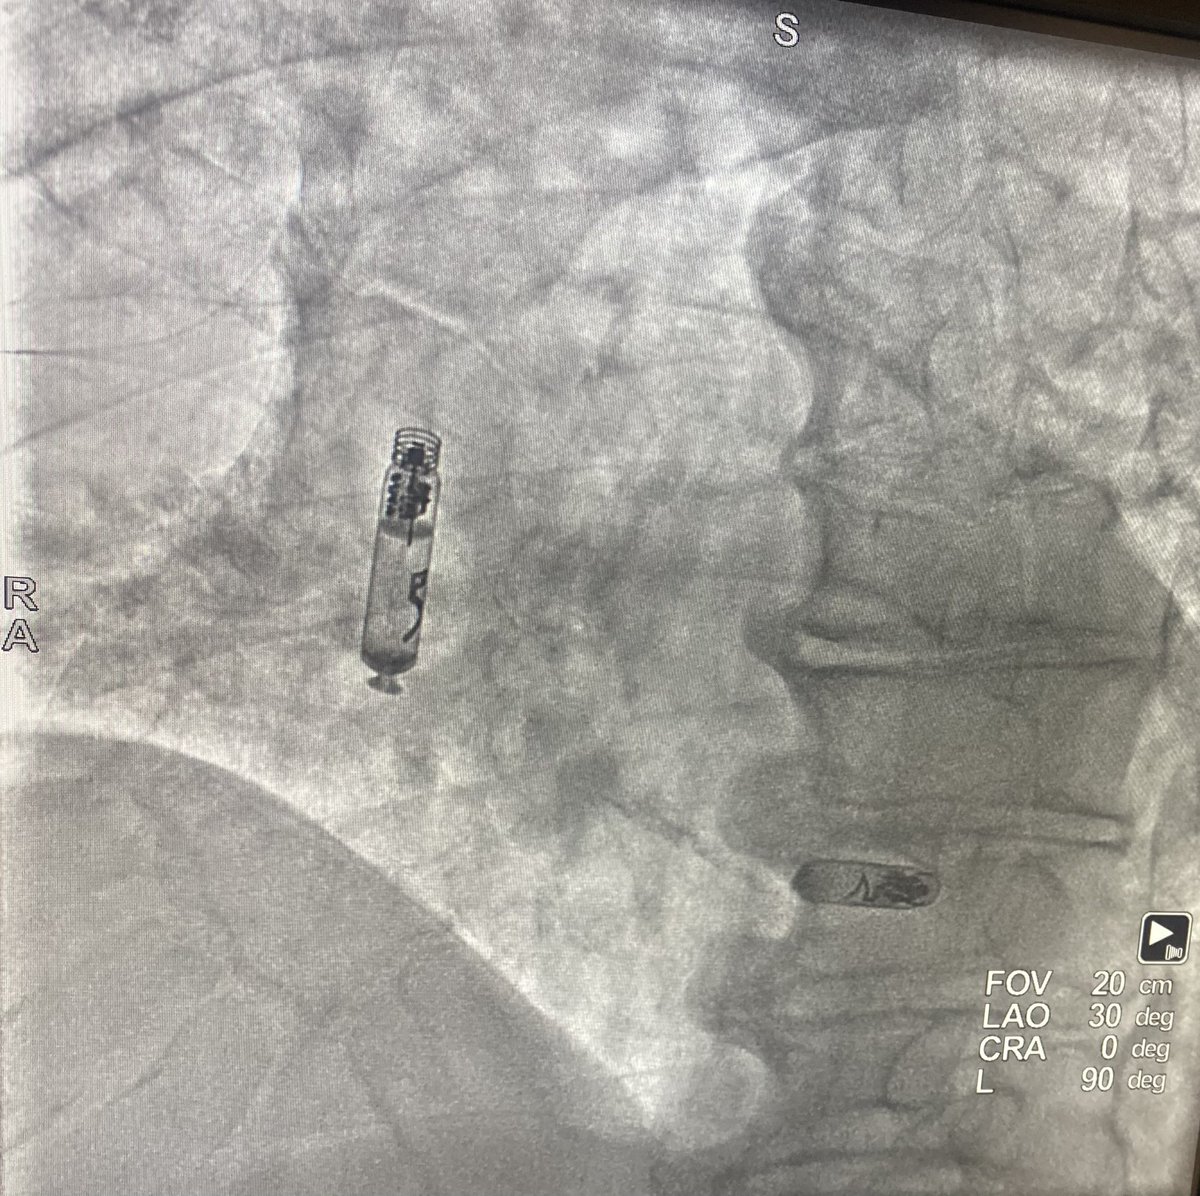

First #Farapulse Pulsed field ablation case at Aurora St. Luke's Medical Center using NAVIK technology integrating 3D mapping and fluoroscopy for better visualization of the Farawave catheter using 2D -3D fluoro and non fluoro mapping integrated with fluoro 3D location.